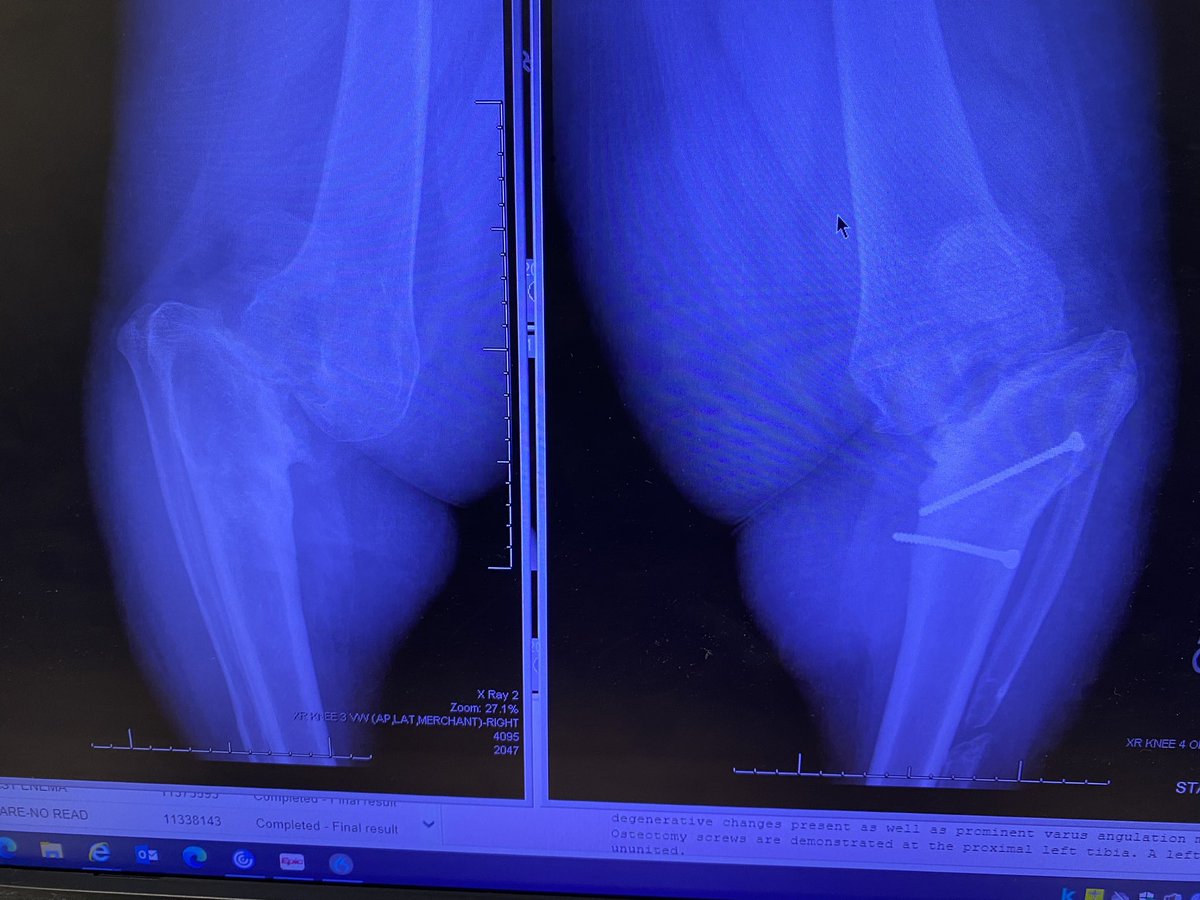

Would love to get thoughts on this case. 41y/o female from Nigeria. Bilateral knee pain and previous surgeries. Skin very thin and tenuous. #orthotwitter @jointdocShields @DrLeeRubin @BoneDocMMD @CoryCalendineMD @_NancyMD @rkh_md @Dr_Stambough and everyone else

wanting TKA. Allergy to nickel and cement on now two different patch tests. Yes not perfect test but I live in colorado so a real thing here. Benign enchondroma in tibia. How are you dealing with this?? @BoneDocMMD @DrLeeRubin @jointdocShields @generalorthomd @RafaSierra5

Tough case @jointdocShields @EdinburghKnee @DrLeeRubin @BoneDocMMD and whomever else couldn’t add everyone #61y/o physician. Wants TKA. Deformity and remote infection. Infection workup negative. Stage? All at once? Or patient is enquiring about DFR. Thx for your thoughts